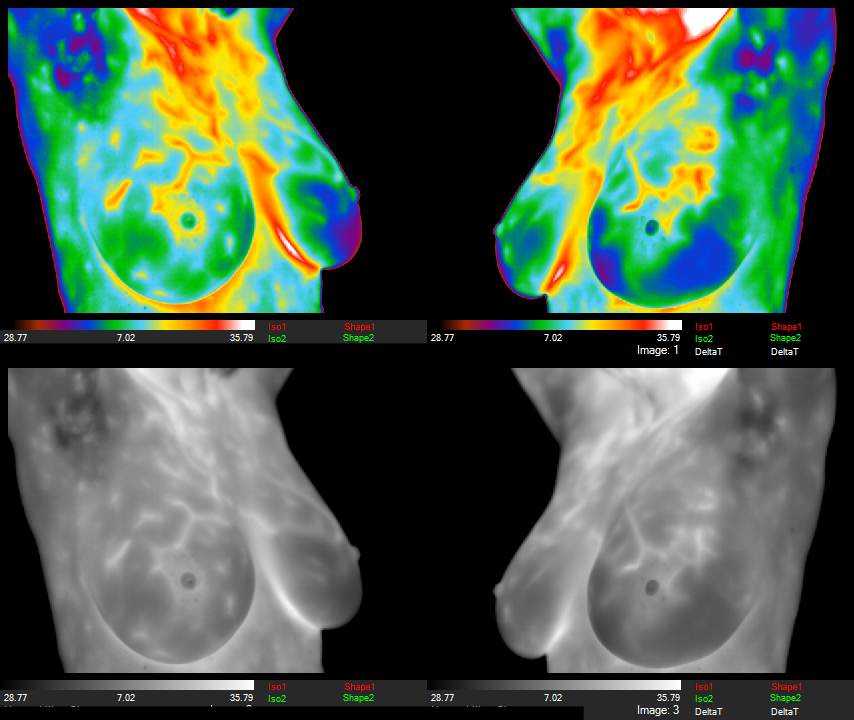

ABNORMAL Left Breast REVERSED Plus "Significant Improvement" in the Estrogen Pattern!!!

Risk-Lowering Power of Compounded Progesterone Capsule on Estrogen Dominance in Only 5 Months! Risk Reversal Clear as Day